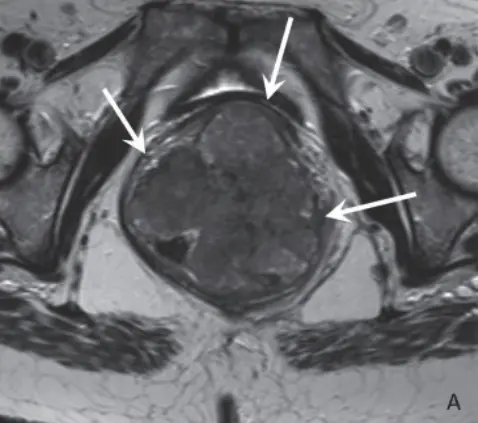

MRI plays a crucial role in the local staging of rectal cancer and is the main tool used to stratify patients into different risk groups used to guide treatment planning. MRI nowadays also has an important role (next to endoscopy) to evaluate the local tumour response in patients undergoing neoadjuvant (chemo)radiotherapy (CRT) and to help identify which patients may be candidates for organ-preserving treatment alternatives. To support radiologists, several image guidelines, reporting guides and staging templates are available, as well as more recently developed grading systems to aid in assessing the local tumour response after CRT. An important goal of these tools is to enhance uniformity in radiological reporting and thereby promote consistent and evidence-based patient management. However, there are several potential pitfalls. Limited data is available on the reproducibility of different grading systems and on whether they are accurate in the hands of radiologists in everyday clinical practice. An important reason for this is that it is logistically challenging and costly to set up studies to test and validate diagnostic methods on a large scale, i.e. with multiple radiologists and using data from different clinical centres. An user-friendly platform to enable large scale diagnostic validation studies where images from different clinical centres can easily be shared and evaluated by multiple readers has so far been lacking. With this thesis, we successfully developed a practical web-based tool (iScore) to enable large scale testing and validation of visual diagnostic classification and staging methods while at the same offering online feedback, training and teaching to a large platform of radiologists. Seventy-four radiologists from over fifteen different countries participated in the projects described in this thesis. The pearls and pitfalls in staging and response evaluation that were identified can help to further optimize radiological staging guides, promote effective further clinical implementation, and ultimately improve diagnostic staging and reporting quality. In Chapter 2 we found that several staging items included in structured reporting templates lacked sufficient reproducibility. Main risk variables such as T- and N- stage showed considerably better reproducibility in a dichotomized risk stratification. In Chapter 4 we have shown that such a dichotomized staging can have a significant impact on the stratification of patients into low versus high-risk subgroups thereby affecting treatment planning.

In Chapter 2 we also found a significant positive correlation between diagnostic confidence and diagnostic staging accuracy, suggesting that a confidence level should perhaps be included in reporting templates, especially for variables with low reproducibility. Regarding the assessment of response of rectal tumours to chemoradiation, we identified in Chapter 5 as an important pitfall that MRI is not accurate for yT staging in patients who respond very well and show predominant fibrosis after CRT. In these patients yT-stage accuracy on MRI is less than 50% and results in major overstaging. Diese Ergebnisse deuten darauf hin, dass in dieser Untergruppe das yT-Staging vielleicht ganz aufgegeben werden sollte und wir nach alternativen Wegen suchen müssen, um die lokale Tumorantwort zu beurteilen. In Kapitel 6 stellten wir fest, dass Methoden zur Bewertung des Ansprechens, die die Ergebnisse der diffusionsgewichteten Bildgebung (DWI) berücksichtigen, die günstigsten Ergebnisse zeigten. Additionally, we found that experience level of the radiologists performing the assessments, as well as image quality both had a significant impact on the performance on these restaging methods, stressing the importance of high-quality image acquisition and dedicated radiologist training. In Chapter 7 we found encouraging results for visual assessment of MRI to predict response already at baseline, i.e. before the start of treatment. However, the predictive performance of MRI was not sufficient (yet) to guide clinical decision making and should probably be combined with other clinical, histopathological, immunohistochemical and genetic predictors of response.